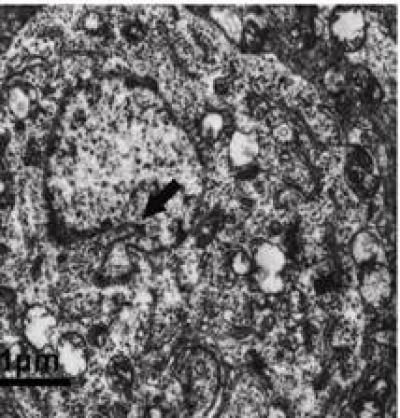

Hypoxia-inducible factor 1 (HIF-1) attenuates amyloid-beta protein neurotoxicity and decreases apoptosis induced by oxidative stress or hypoxia in cortical neurons. Prof. Xiqing Chai and co-workers from Hebei Chemical and Pharmaceutical College, China constructed a recombinant adeno-associated virus (rAAV) vector expressing the human HIF-1α gene (rAAV-HIF-1α) efficiently, and tested the assumption that rAAV-HIF-1α represses hippocampal neuronal apoptosis induced by amyloid-beta protein. Their results confirmed that rAAV-HIF-1α significantly reduces apoptosis induced by amyloid-beta protein in primary cultured hippocampal neurons. This mechanism may be related to HIF-1α-decreased hippocampal neuronal intracellular calcium concentration ([Ca2+]i), thereby inhibiting apoptotic cascade reactions. With these investigations published in the Neural Regeneration Research (Vol. 9, No. 11, 2014), gene therapy using rAAV to deliver HIF-1α may ultimately provide a new option for clinical treatment of Alzheimer's disease.

Article: " A viral vector expressing hypoxia-inducible factor 1 alpha inhibits hippocampal neuronal apoptosis," by Xiqing Chai1, Weina Kong1, Lingyun Liu2, Wenguo Yu1, Zhenqing Zhang3, Yimin Sun1 (1 Bioreactor and Protein Drug Research and Development Center of Hebei Universities, Hebei Chemical and Pharmaceutical College, Shijiazhuang, Hebei Province, China; 2 Department of Neurology, Shanghai Yangpu District Central Hospital, Shanghai, China; 3 Department of Neurology, the First Hospital of Hebei Medical University, Shijiazhuang, Hebei Province, China) Chai XQ, Kong WN, Liu LY, Yu WG, Zhang ZQ, Sun YM. A viral vector expressing hypoxia-inducible factor 1 alpha inhibits hippocampal neuronal apoptosis. Neural Regen Res. 2014;9(11):1145-1153.